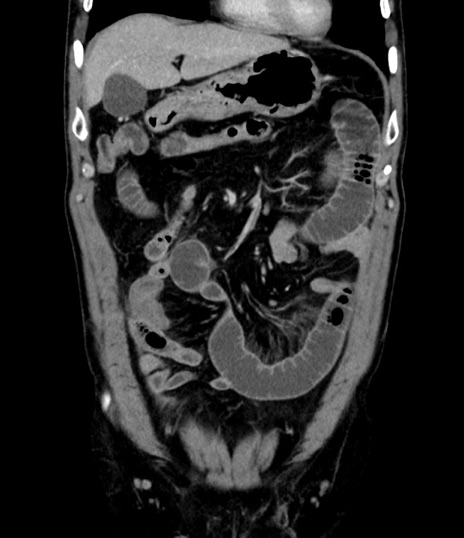

症例8(冠状断像)

【症例】 60歳代男性

【主訴】 黒色吐物

【現病歴】 4日前から嘔気自覚、2日前の朝食後にも嘔気あり、自分で手で嘔吐反射起こし嘔吐したところ血が混ざっていたため受診。

【既往歴】 5年前汎発性腹膜炎を伴う急性虫垂炎で手術、高血圧、前立腺肥大症、高脂血症

【身体所見】 腹部正中に手術癩痕あり 腹部平坦・軟圧痛なし膨満感あり

【データ】WBC 8400、CRP 4.54